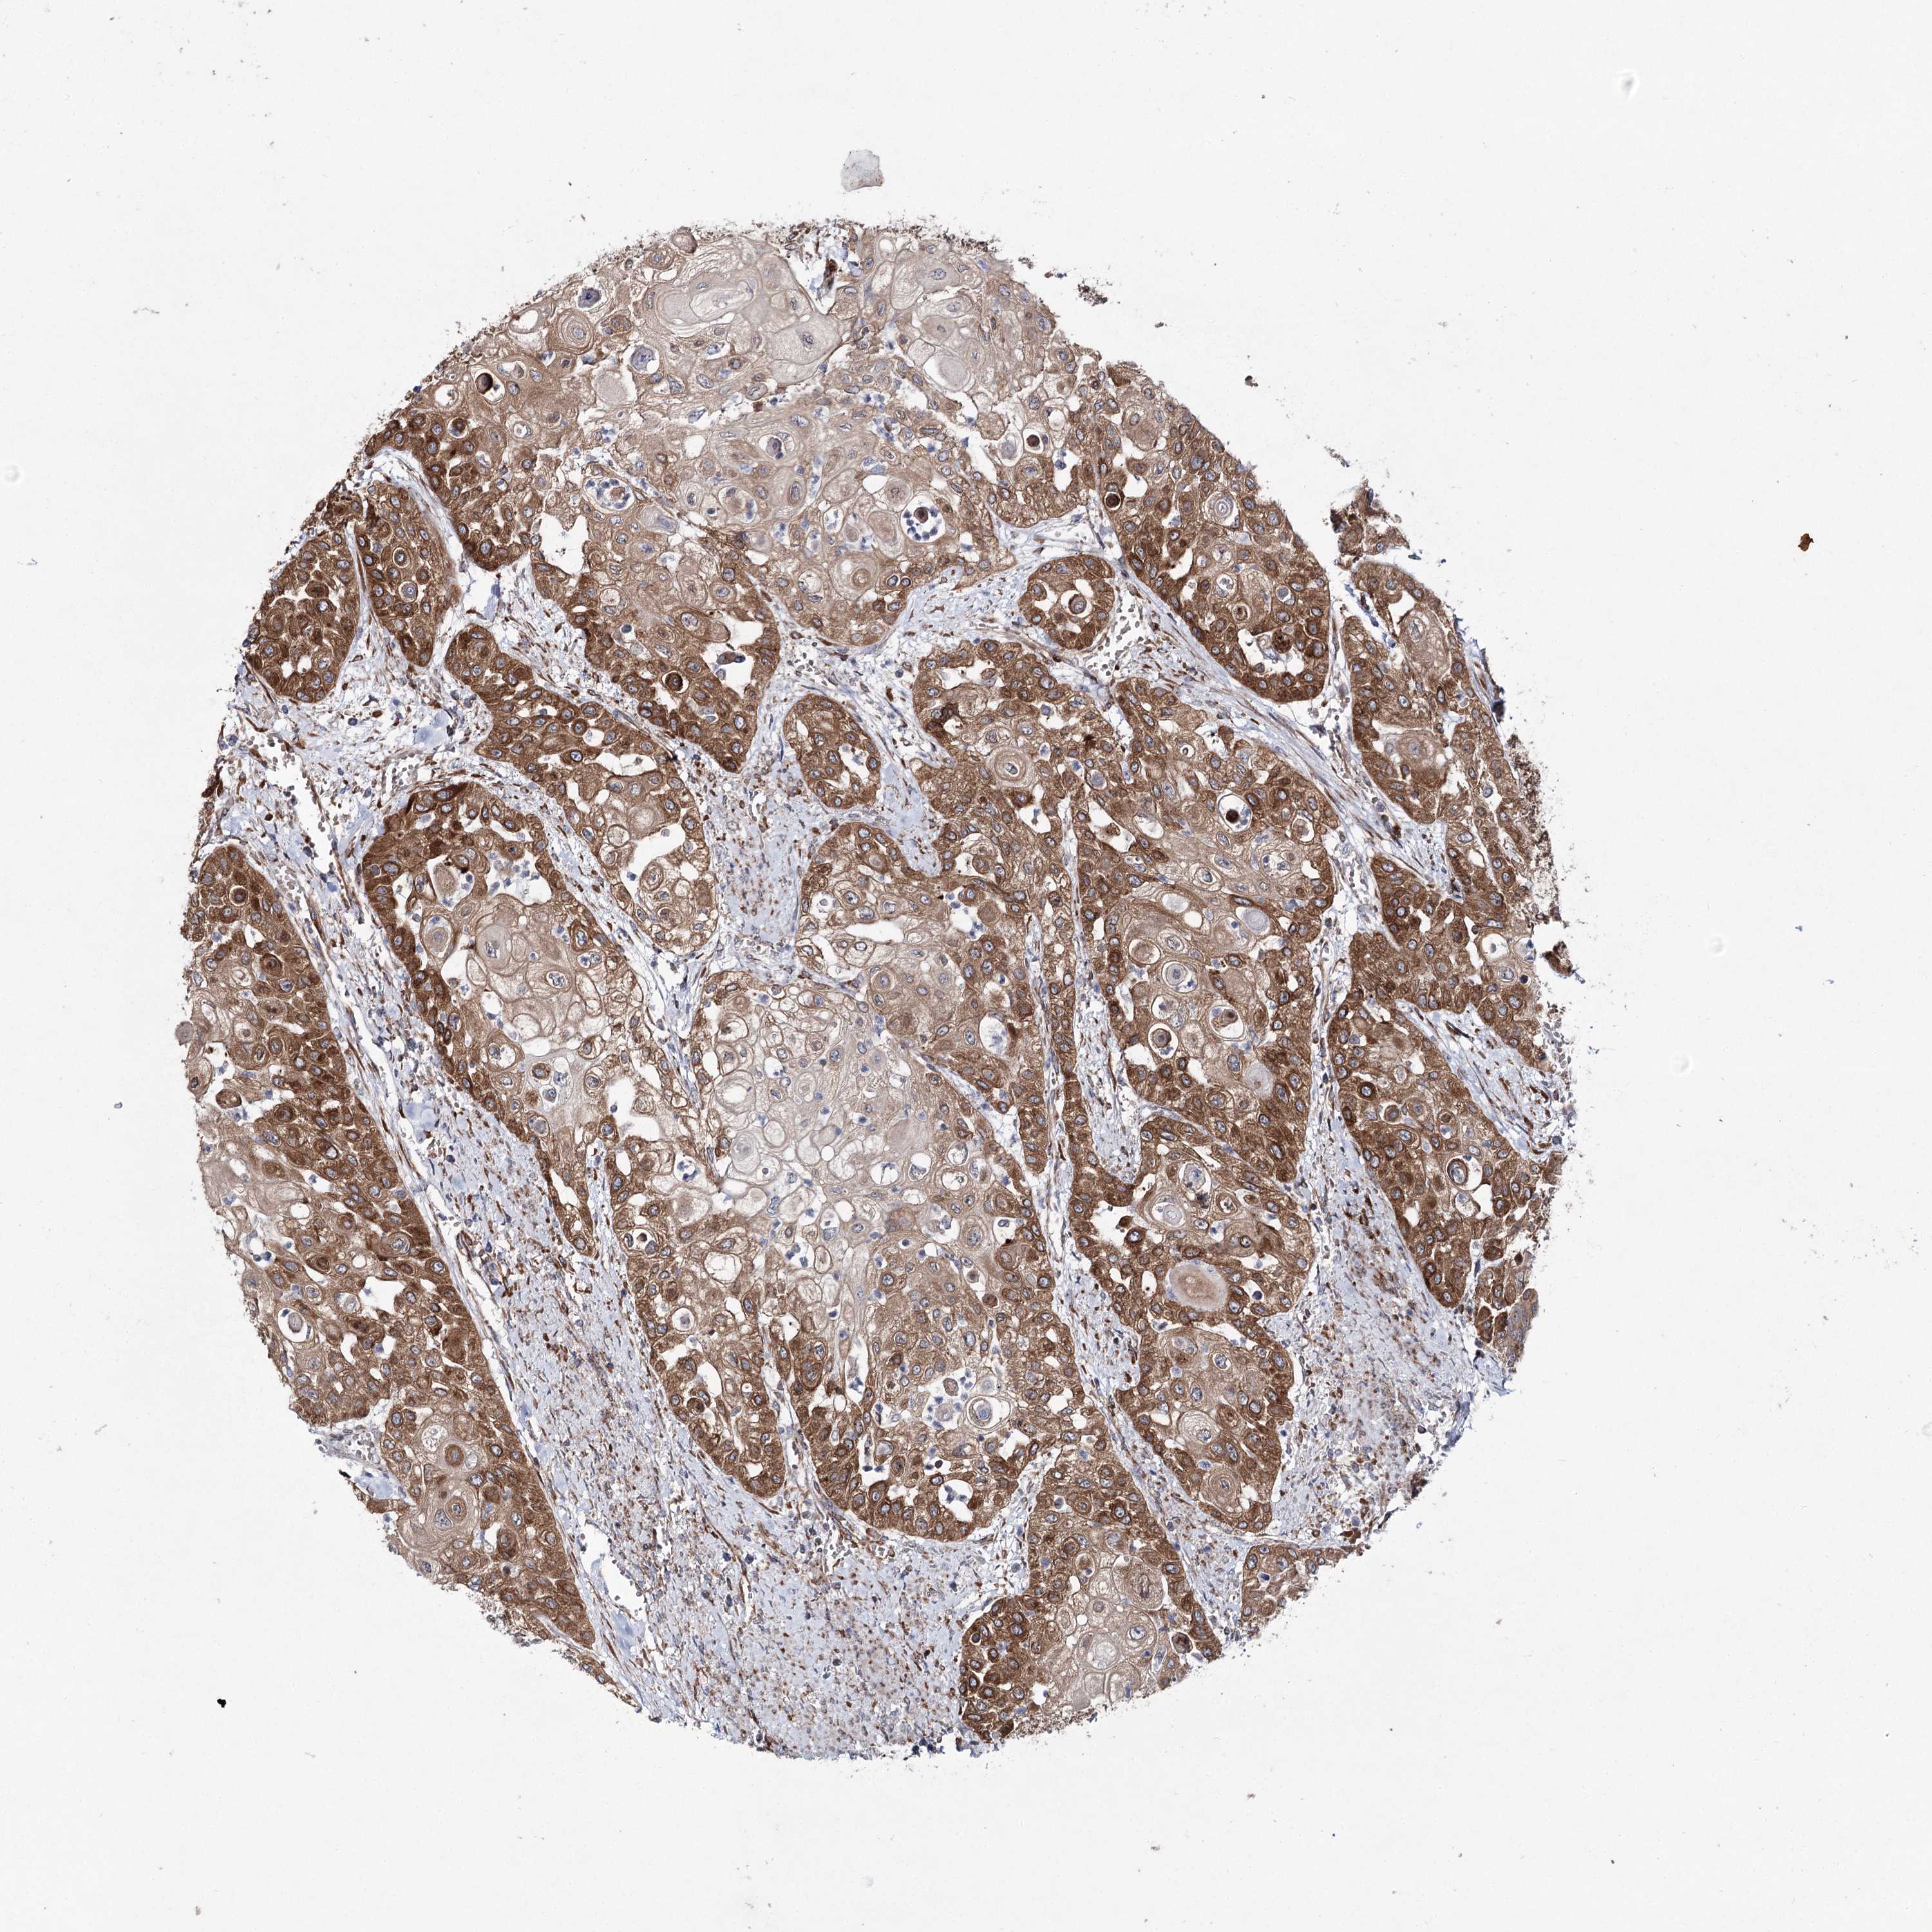

UROTHELIAL CANCER - Protein expressioni

A mouse-over function shows sample information and annotation data. Click on an image to view it in a full screen mode. Samples can be filtered based on level of antibody staining by selecting one or several of the following categories: high, medium, low and not detected. The assay and annotation is described here.

Note that samples used for immunohistochemistry by the Human Protein Atlas do not correspond to samples in the TCGA dataset.

Antibody stainingi

Antibody staining in the annotated cell types in the current human tissue is reported as not detected, low, medium, or high, based on conventional immunohistochemistry profiling in selected tissues. This score is based on the combination of the staining intensity and fraction of stained cells.

Each image is clickable and will lead to virtual microscopy that enables deeper exploration of all samples and also displays staining intensity scores, fraction scores and subcellular localization as well as patient and tissue information for each sample.

Antibody HPA037847

Staining

High

Medium

Low

Not detected

Intensity

Strong

Moderate

Weak

Negative

Quantity

>75%

75%-25%

<25%

None

Location

Nuclear

Cytoplasmic/membranous

Cytoplasmic/membranous,nuclear

Urothelial carcinoma, High grade

Urothelial carcinoma, Low grade

Urothelial carcinoma, NOS